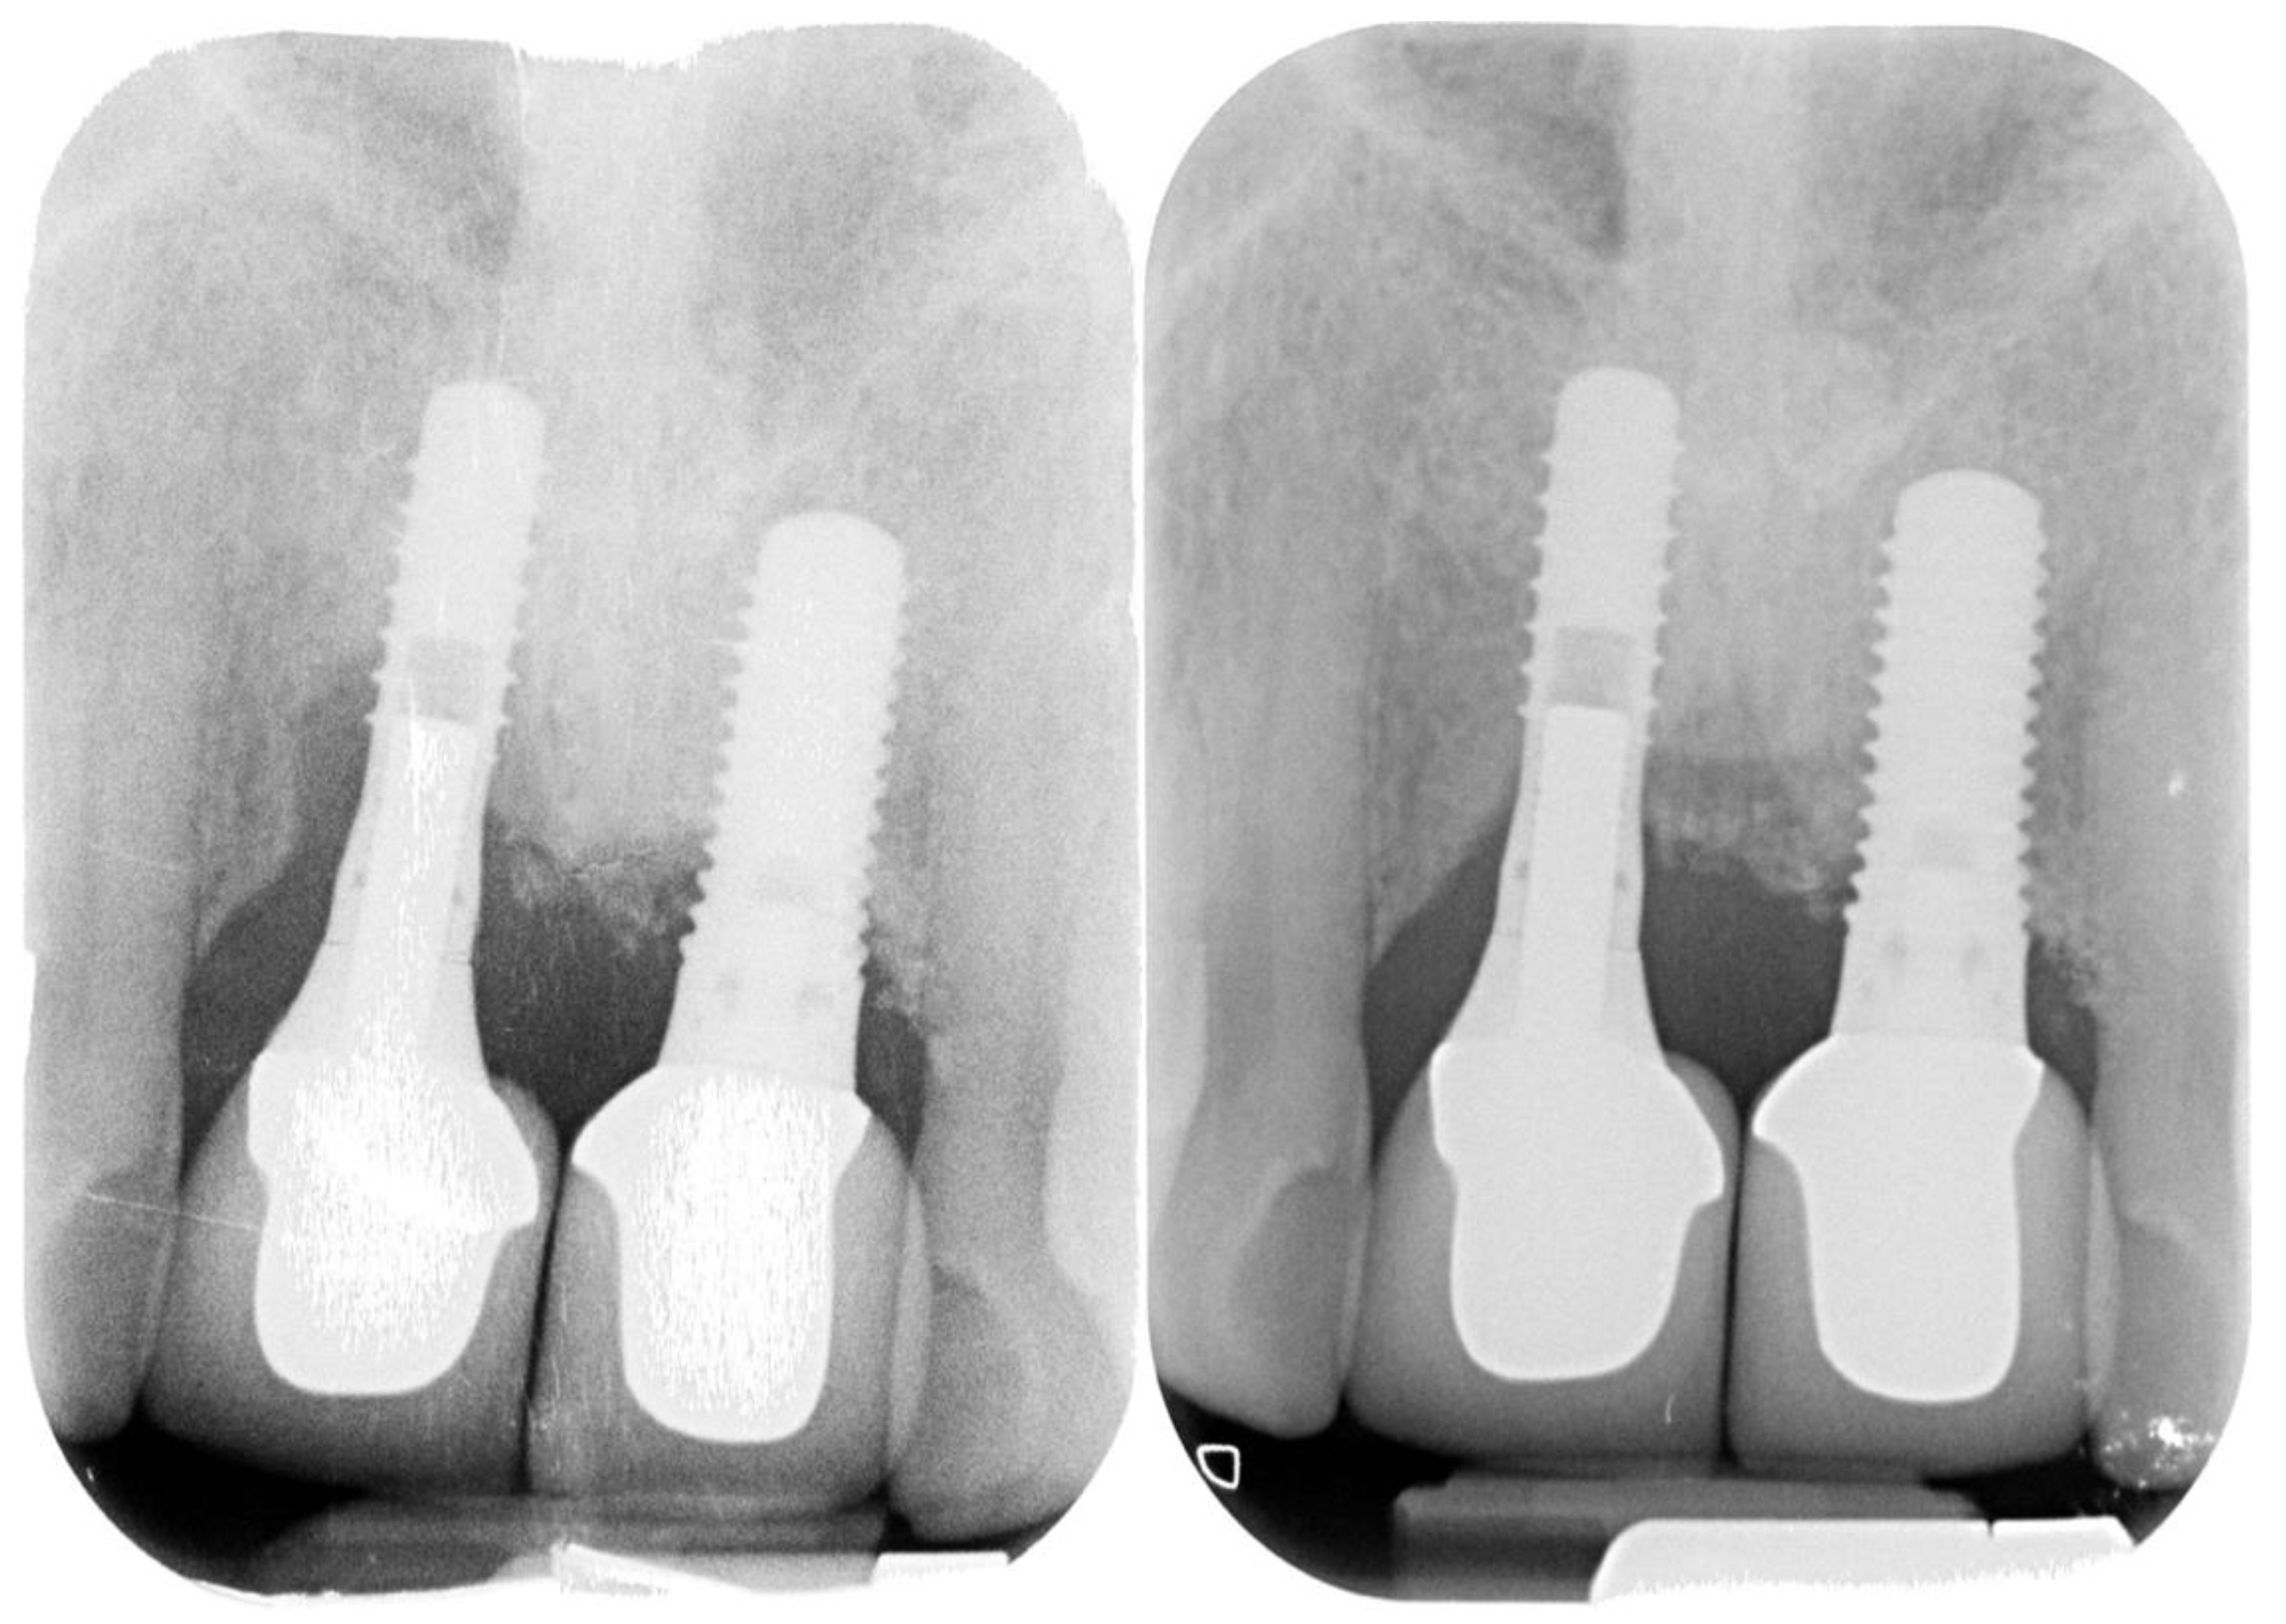

Peri-Implantitis: Application of a Protocol for the Regeneration of Deep Osseous Defects. A Retrospective Case Series

2. Materials and Methods